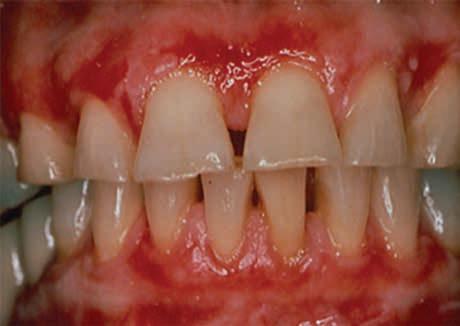

Mucous Membrane Pemphigoid

Figures 3-5. Mucous membrane pemphigoid (MMP) presenting as desquamative gingivitis; poor plaque control resulting from the inability to brush comfortably; patient responded well to topical steroids applied in delivery trays. Figure 3 Figure 4 Figure 5